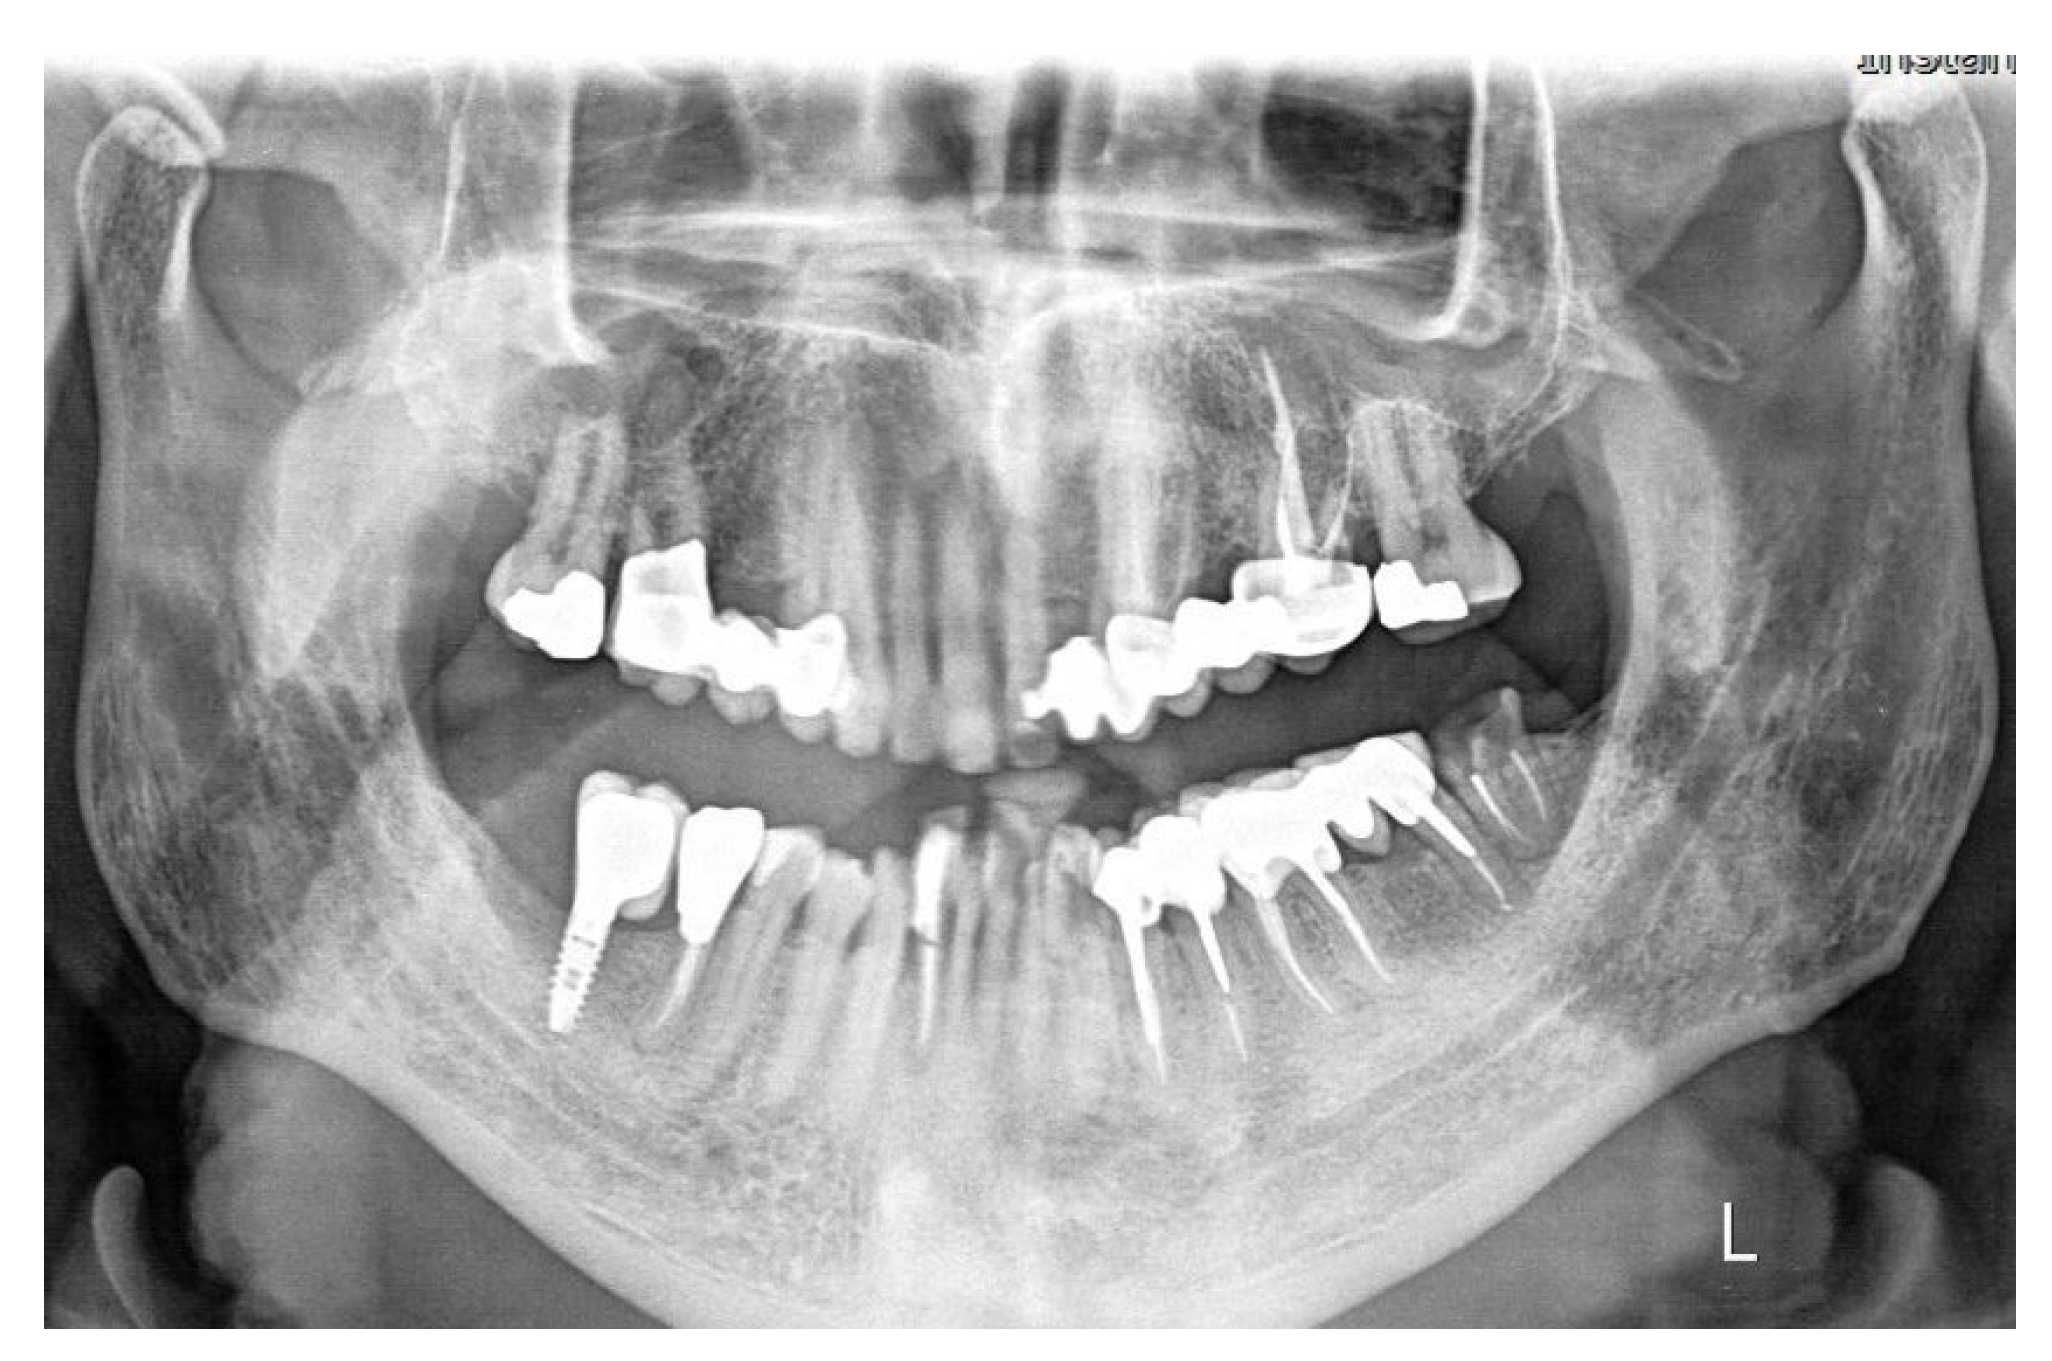

From radiographic examination with OPT (Figure 1) a moderate periodontal bone loss on the lower right side of the patient was observed.

Figure 1. Initial OPT X-Ray.